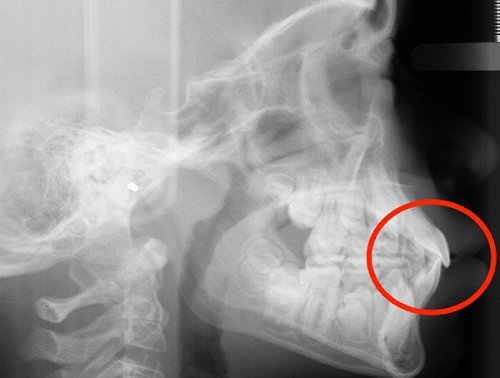

Actual Patient: Alexander

Alexander Before 4 Alexander After 4

Severe “Underbite”, Narrow Jaws, Adult Teeth Not Growing In

Alexander Before 1 Alexander After 1

Front View Results

0 Month

6 Month

11 Month

Side View Results